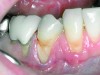

Following active therapy, probing depths of 4 mm or less (Figure 1 and Figure 2) and the absence of bleeding on probing contribute to improved health and stability. Increasing probing depths should alert the therapist to identify etiology and determine whether active periodontal therapy is warranted. The absence of bleeding on probing is a strong predictor of stability, and although the presence of bleeding does not always result in attachment loss, it remains an important parameter to evaluate.14 Bleeding on probing is also an important parameter for assessing implant health during maintenance. Serino et al15 evaluated 27 patients with 19 dental implants over 5 years. Patients were seen every 6 months and they concluded that bleeding on probing was a good predictor for attachment loss and disease progression around the implants (Figure 3).

Fig 1. A deep pocket of 7 mm prior to active periodontal therapy.

Figure 1

Fig 2. Following periodontal regenerative therapy, the tooth with a 3-mm probing depth, which facilitates maintenance.

Figure 2